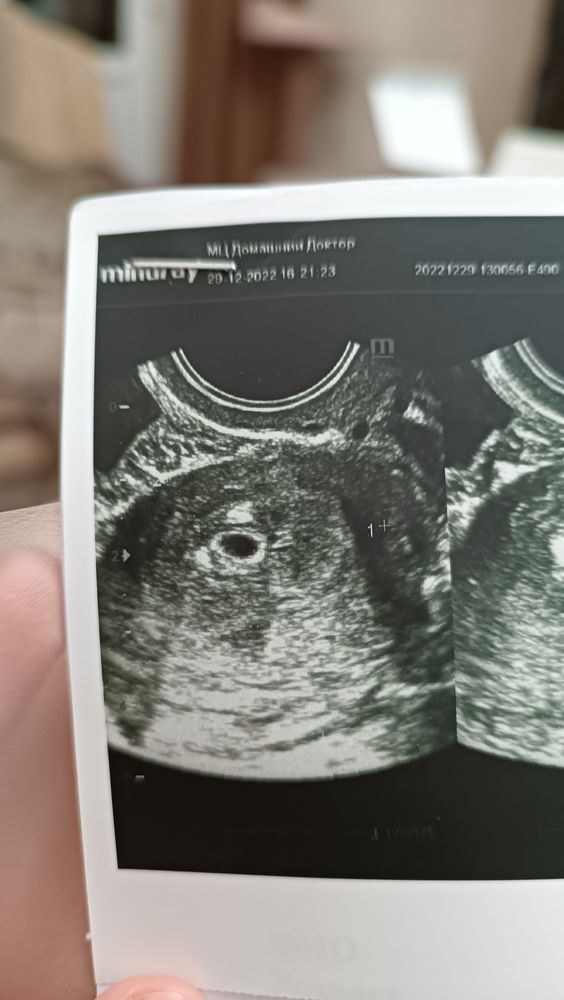

УЗИ на 5 неделе

Первое УЗИ 🥰🙏 Девочки, апокалипсис какой то😹